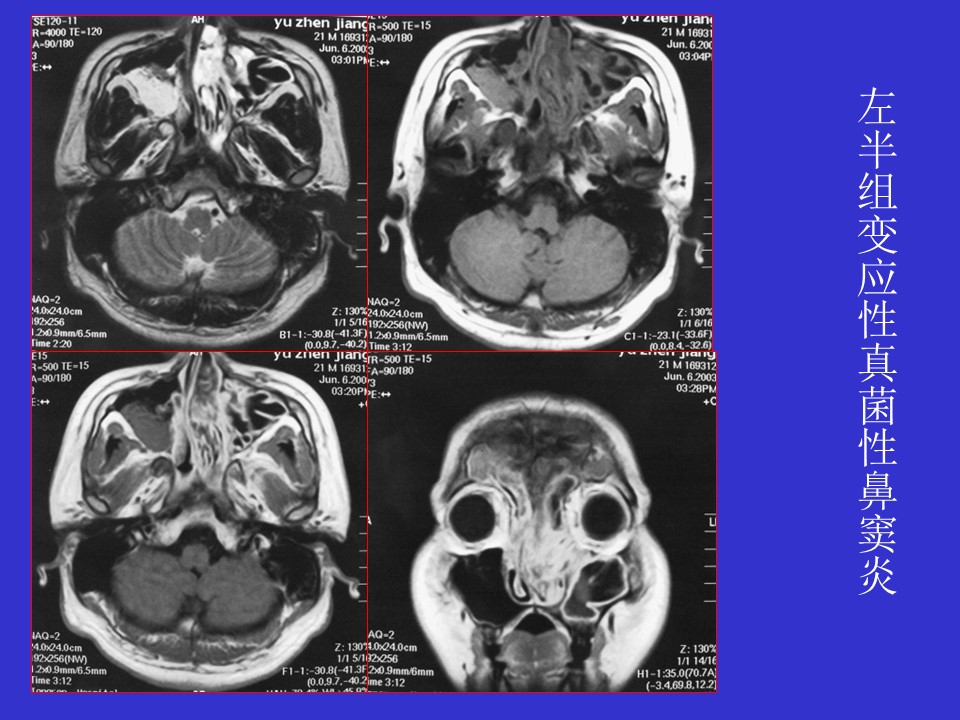

“真菌性鼻窦炎影像学诊断PPT” 的相关文章